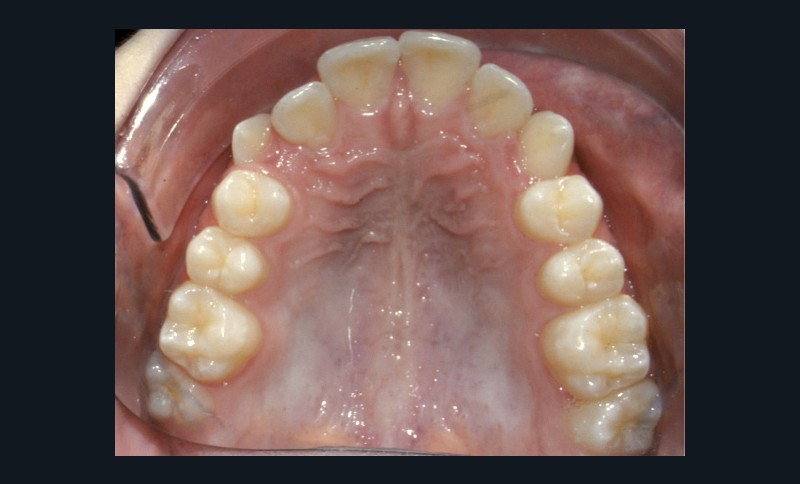

Examen endo-buccal (fig. 2a-e)

L’arcade maxillaire est parabolique avec une mésio-rotation de 16 et 26, une vestibulo-position de 17 et une infra-vestibulo-position de 13 et 23. L’encombrement est estimé à 7 mm.